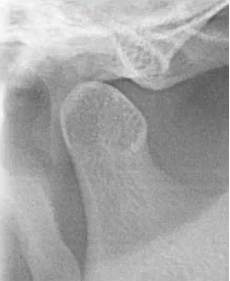

6. 颞下颌关节:髁突外形

比如患者右侧髁突的前斜面发生了硬骨改变。

比如这位患者,当我们在曲面断层片发现有关节髁突的外形改变,就会指引临床大夫做颞下颌关节检查,比如看一下颞下颌关节的张口度、对称性,关节是否有弹响等,必要时需要做颞下颌关节CBCT。

甚至当我们怀疑关节盘有问题时,还需要让患者做磁共振,看下是否有关节盘移位等情况。